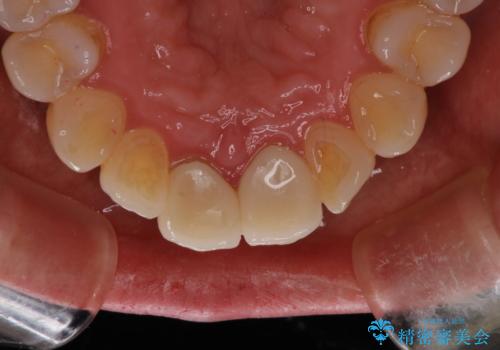

被せ物の治療と歯肉のお掃除にも通っていただいたので、短期間で全体的に綺麗になったと喜んでいました。